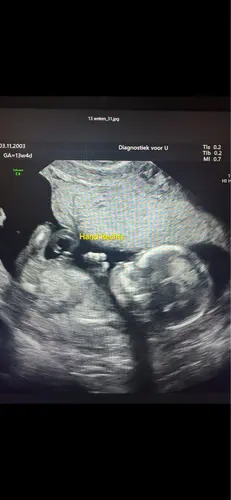

Je exho fotos zijn heel lelijk. Kun je bij jou in het zkh inloggen in je patientdossier? Bij mij stonden hier meer fotos dan degenen die ik mee had gekregen.

Maar de echo’s die jij hebt gekregen zijn wel echt van hele slechte kwaliteit ☹️ de foto’s die ik meekrijg uit het ziekenhuis zijn wel met zorg en aandacht gemaakt. Vervelend voor je! Ik zou het de volgende keer wel gewoon aangeven hoor want dit is niet leuk